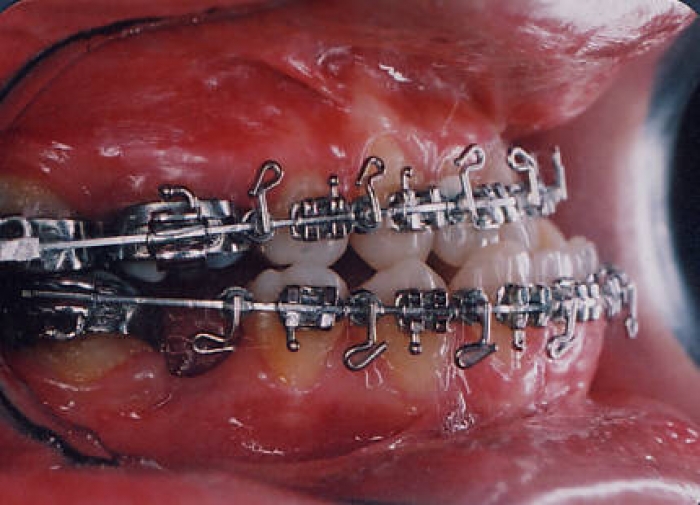

Mordida inicial